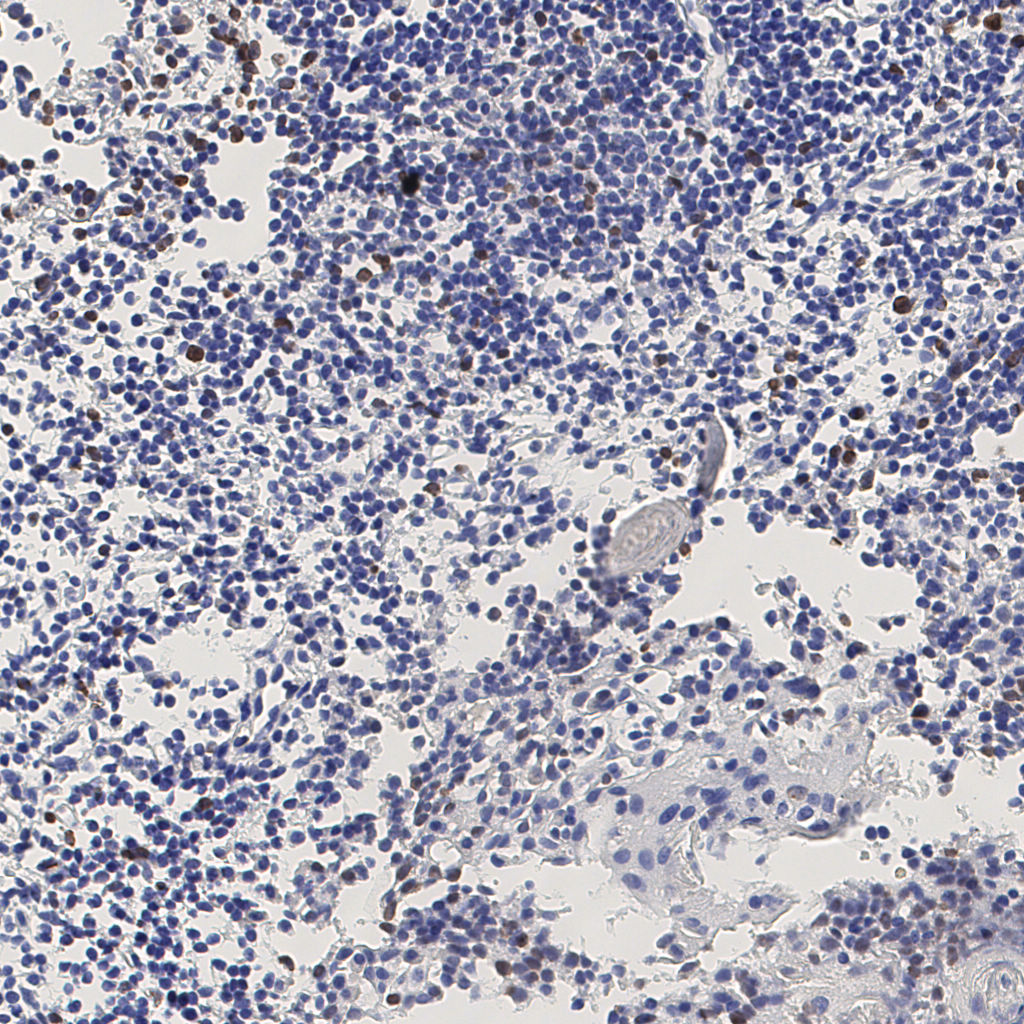

7.85%

Ki67 指数

阴 1104

阳 94

标记后

标记前